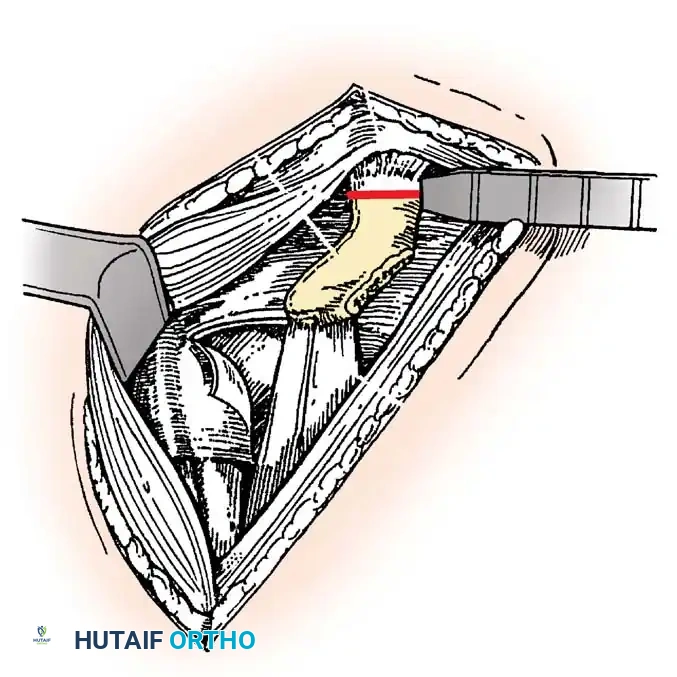

Subscapularis Management

Exposure of the anterior capsule requires navigating the subscapularis muscle. Historically, a vertical tenotomy was performed; however, modern techniques favor a subscapularis split or a peel to preserve the integrity of the muscle belly and its tendinous insertion.

- The Split: A horizontal split is made in the subscapularis at the junction of its middle and inferior thirds, extending from the lesser tuberosity medially.

- Separation: The subscapularis is carefully elevated off the underlying anterior joint capsule. This plane can be scarred in revision cases, requiring meticulous sharp dissection to avoid inadvertent capsulotomy.